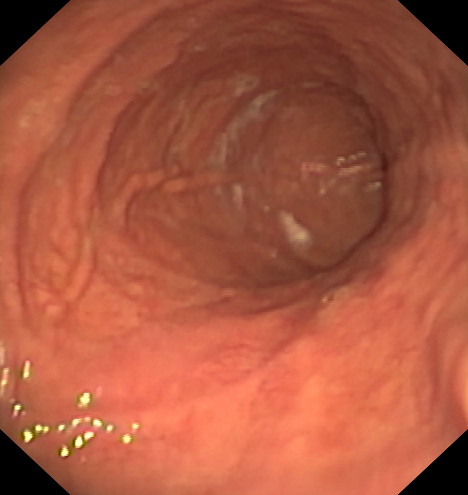

BALÓN INTRAGÁSTRICO

El balón intragástrico es un implante temporal de silicona, que rellenamos con suero, normalmente unos 500-600 cc, con un colorante (azul de metileno) para detectar cualquier posible anomalía futura (pérdida de contenido o rotura), una vez se aloja en el estómago y ocupa una parte importante del mismo. Esto genera dos mecanismos clave para aumentar la saciedad y por ello, perder peso:

- Ocupación de espacio: El dispositivo se aloja libremente en el estómago y genera ya de por sí una sensación de saciedad, ya que tiene entre 10 y 12 cm de diámetro.

- Enlentece la digestión de la comida: El balón dificulta el paso de la comida hacia el intestino, haciendo el proceso más largo en el tiempo. En condiciones normales, la comida tarda una hora aproximadamente en digerirse y pasar al intestino en donde se absorbe. En este caso, la comida permanece más tiempo en el estómago y hace que la saciedad se mantenga más tiempo, ayudando a no pasar hambre, sobre todo en el momento más crítico del día, que suelen ser las horas vespertinas.

Está indicado, como primera opción terapéutica, para pacientes con obesidad leve-moderada (IMC entre 30 y 35) o pacientes con IMC entre 35 y 40 que rechazan otros procedimientos.

Su colocación se realiza en la mayoría de las ocasiones por gastroscopia con sedación profunda administrada y controlada por anestesista, siendo una técnica ambulatoria (no precisa ingreso hospitalario) y su retirada, tras haber cumplido su función a los 6-12 meses, dependiendo de cada caso concreto, por gastroscopia con intubación y anestesista general, para minimizar los posibles inconveniente inherentes a la técnica, igualmente de forma ambulatoria.

La pérdida de peso suele situarse entre los 20-25 kg de media, llegando algunos pacientes a perder más de 35-40 kg, dependiendo del tipo de balón empleado (de 6 o 12 meses), pero puede tener el inconveniente de una re-ganancia tras su retirada si antes no se han implementado unos buenos hábitos higiénicos y dietéticos, siendo aconsejable desde su inicio el asesoramiento por endocrino, nutricionista y/o psicólogo.